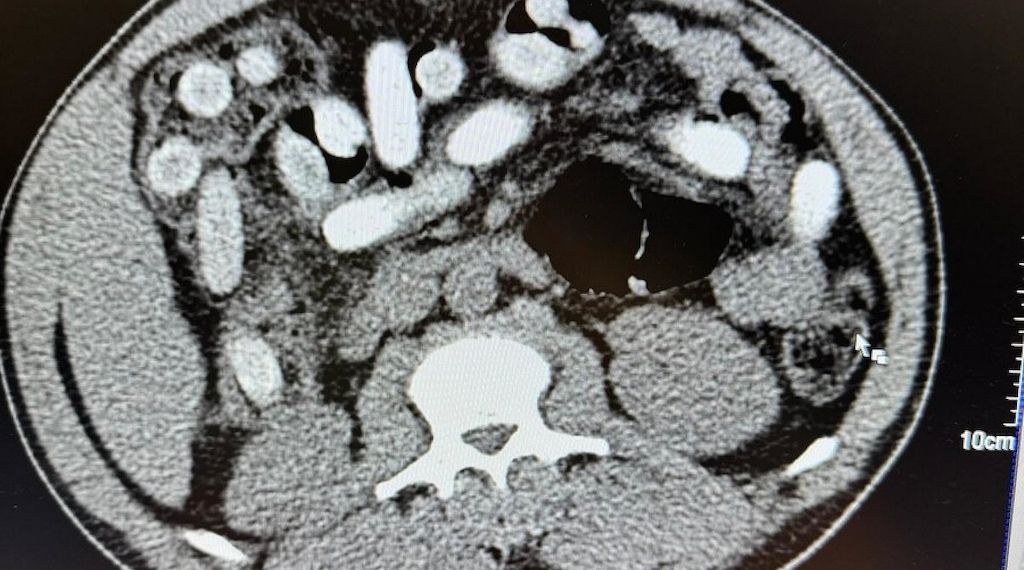

Der Kölner Zoll hat einen Italiener mit rund 1,3 Kilogramm Kokain im Magen-Darm-Trakt festgenommen. Der 50-Jährige war Ende Januar in einem Reisebus auf der A3 zwischen Bonn und Köln unterwegs, als Beamte ihn aufgrund widersprüchlicher Angaben und auffälligen Verhaltens kontrollierten, teilte der Zoll am Dienstag mit. Ein Drogentest an den Händen schlug positiv an, ein Röntgenbild bestätigte später 111 verschluckte Kokain-Päckchen. "Rund 1,3 Kilogramm Kokain versteckt im Körper ist für uns ein neuer trauriger Rekord", sagte Jens Ahland, Pressesprecher des Hauptzollamts Köln.